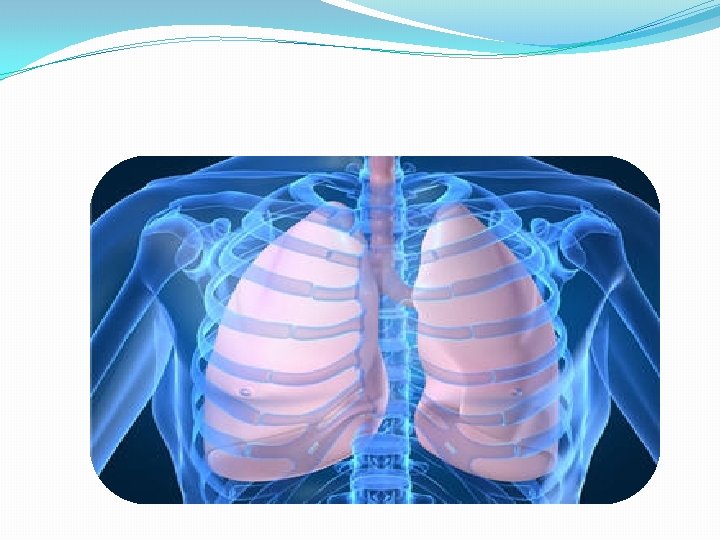

ESPACIO PLEURAL �Tiene dos hojas (parietal, visceral); es virtual, tiene presión negativa con respecto a la presión atmosférica, lo cual permite la expansión pulmonar. �Se altera por condiciones externas, es decir cuando es ocupado por cualquier condición o elemento, lo que predispone a colapso pulmonar.

CUADRO CLINICO � Cuando se ocupa el espacio pleural se producirá un cuadro clínico respiratorio, por la presencia física que evita la expansion pulmonar lo cual normalmente se hace en un ambiente de presión negativa. También se agrega la condición que cause el hecho, por ejemplo, un hemotórax, neumotórax, quilotórax, neoplasia, etc.

PATOLOGIAS ESP PLEURAL �NEUMOTORAX (aire) �HEMOTORAX (sangre) �HIDROTORAX (agua) �QUILOTORAX(linfa y nutrientes) �PIOTORAX (EMPIEMA)( pus) �Tomara el nombre de la condición O ELEMENTO que ocupe el espacio pleural.